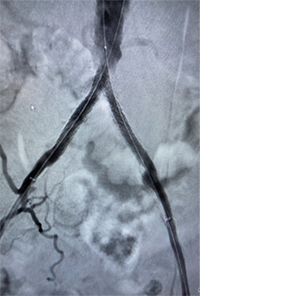

• kissing-stents-placed.png

Pose d’endoprothèses de contact

Images avec l’aimable autorisation du Dr Norby.

Les résultats individuels peuvent varier.